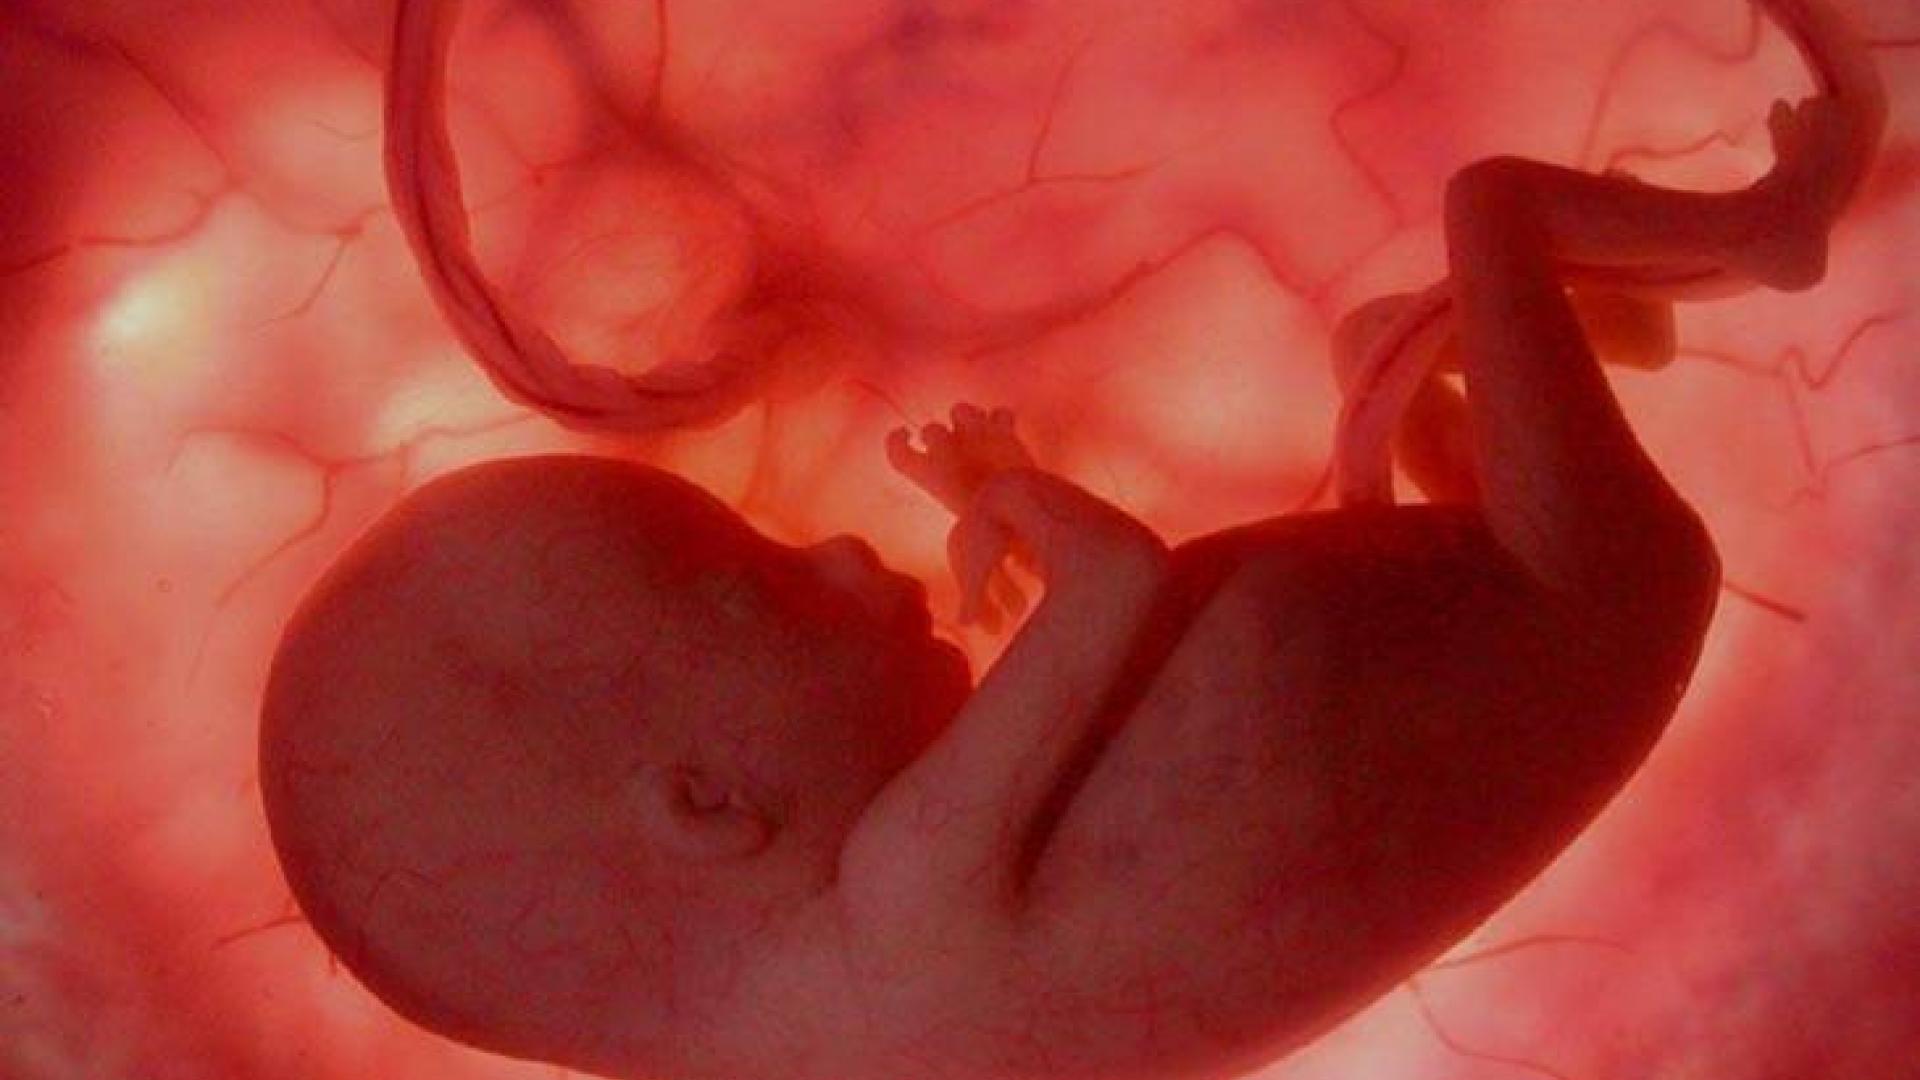

Фотография Плода В Животе

Фотография Плода В Животе 113 фотографий